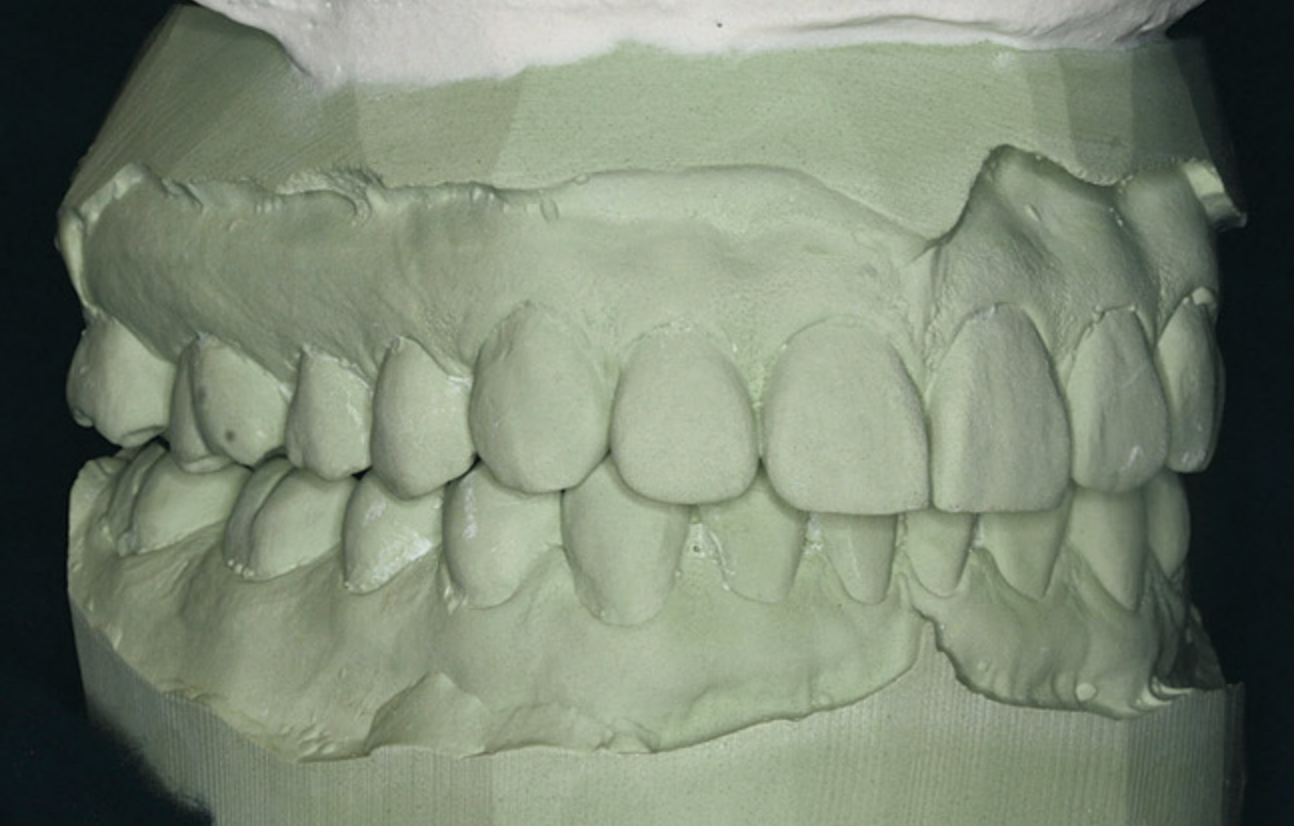

A stable TMJ is critical in establishing a normal functional occlusion. Unless the condyles are in a stable musculoskeletal position, there are always interferences to normal function and stress placed on the masticatory system.1-3,15 In orthodontics, the Angle classification of malocclusion using handheld models has been the standard to evaluate the fit of the teeth. However, it is not possible to truly identify the occlusion/malocclusion using handheld models. Before the occlusion can be evaluated, the clinician must ascertain the joint position and condition (Figure 7 and Figure 8).1,16

Figure 7A  This case is an example of the importance of evaluating the bite with the joints seated in a stable position. Orthodontic treatment was rendered to correct a

Figure 7A

Figure 7B  This case is an example of the importance of evaluating the bite with the joints seated in a stable position. Orthodontic treatment was rendered to correct a

Figure 7B

Figure 7C This case is an example of the importance of evaluating the bite with the joints seated in a stable position. Orthodontic treatment was rendered to correct a

Figure 7C

Figure 7D  This case is an example of the importance of evaluating the bite with the joints seated in a stable position. Orthodontic treatment was rendered to correct a

Figure 7D

Figure 8  Intraoral view of the occlusion of patient from Figure 7 after retreatment. The occlusion is adequate to finish with equilibration.

Figure 8